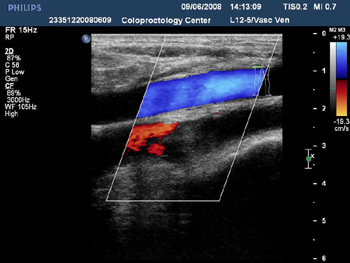

- Дуплексное исследование сосудов конечностей.

- Дуплексное исследование сосудов брюшной полости.